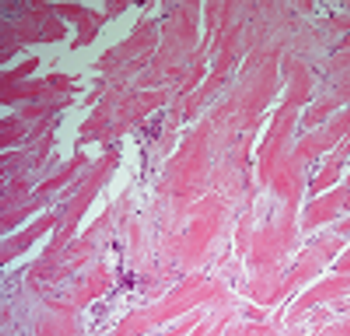

A 43-year-old man presents with a mass lesion in the pelvis, and a biopsy is performed. What is your diagnosis?